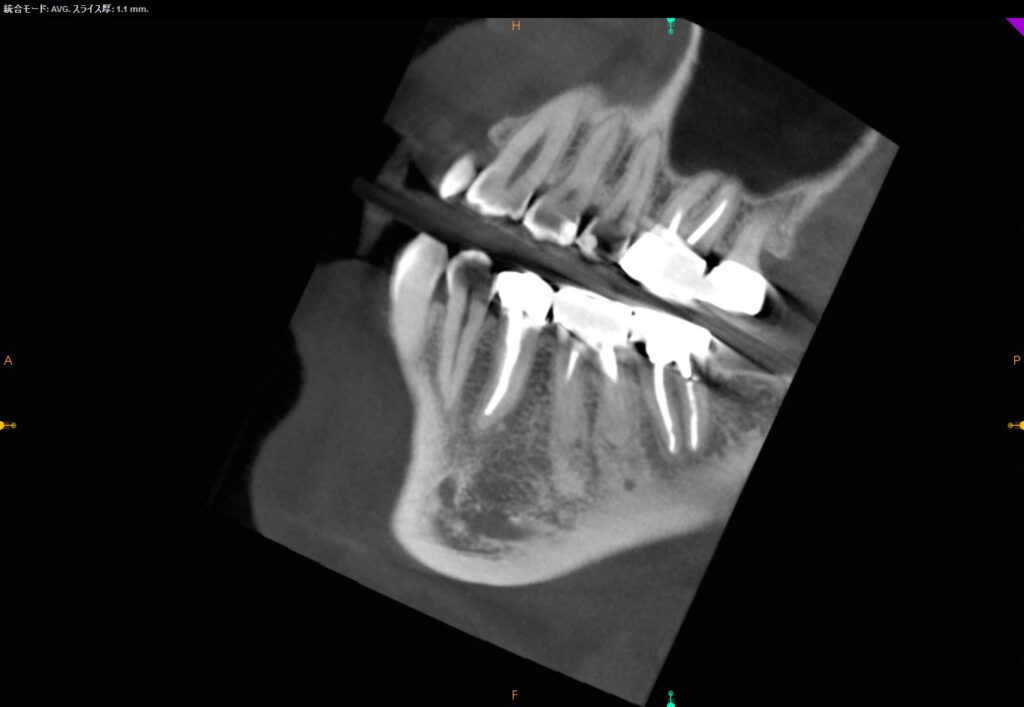

術前CT矢状断

近遠心的(手間から奥に向かって)に、化膿による根っこの先の大きな黒い骨透過像を認めます。手前の左下6番の奥の根っこ(遠心根)の先も化膿していることが分かります。

CT画像矢状断

近遠心的(手間から奥に向かって)に、化膿による根っこの先の大きな黒い骨透過像が改善し、白い骨不透過像を呈していることがはっきりと認められます。すなわち寛解を確認できます。